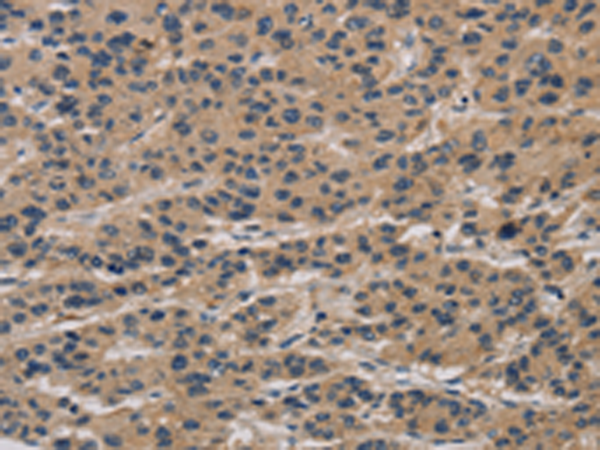

分类: 科研抗体货号: P10778别名: SGS; SKV应用: WB,IHC反应种属: Human, Mouse